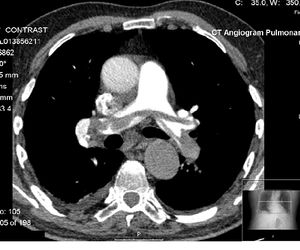

وفي بعض الأحيان، يُحقن في الجسد محلول اليود ويسمى عامل التباين ، حتى يساعد على ظهور أعضاء معيّنة بوضوح في التصوير المقطعي الحاسوبي. ولفحص البطن والحوض، يشرب المريض مزيج الباريوم (الذي لا يُنفِذ الأشعة السينية) لتحديد الأسطح الداخلية للمعدة والأمعاء.

- القلب (مهمة في تشخيص الشريان التاجي، نسبة التكلس مع إصابة ثلاث شرايين)

وتستخدم في تصوير الشريان والأوردة بدل من الأشعة التداخلية وهي أكثر أمانًا وتستغرق وقت قصير وتشخيص الجلطة الرئوية بدل التصوير النووي